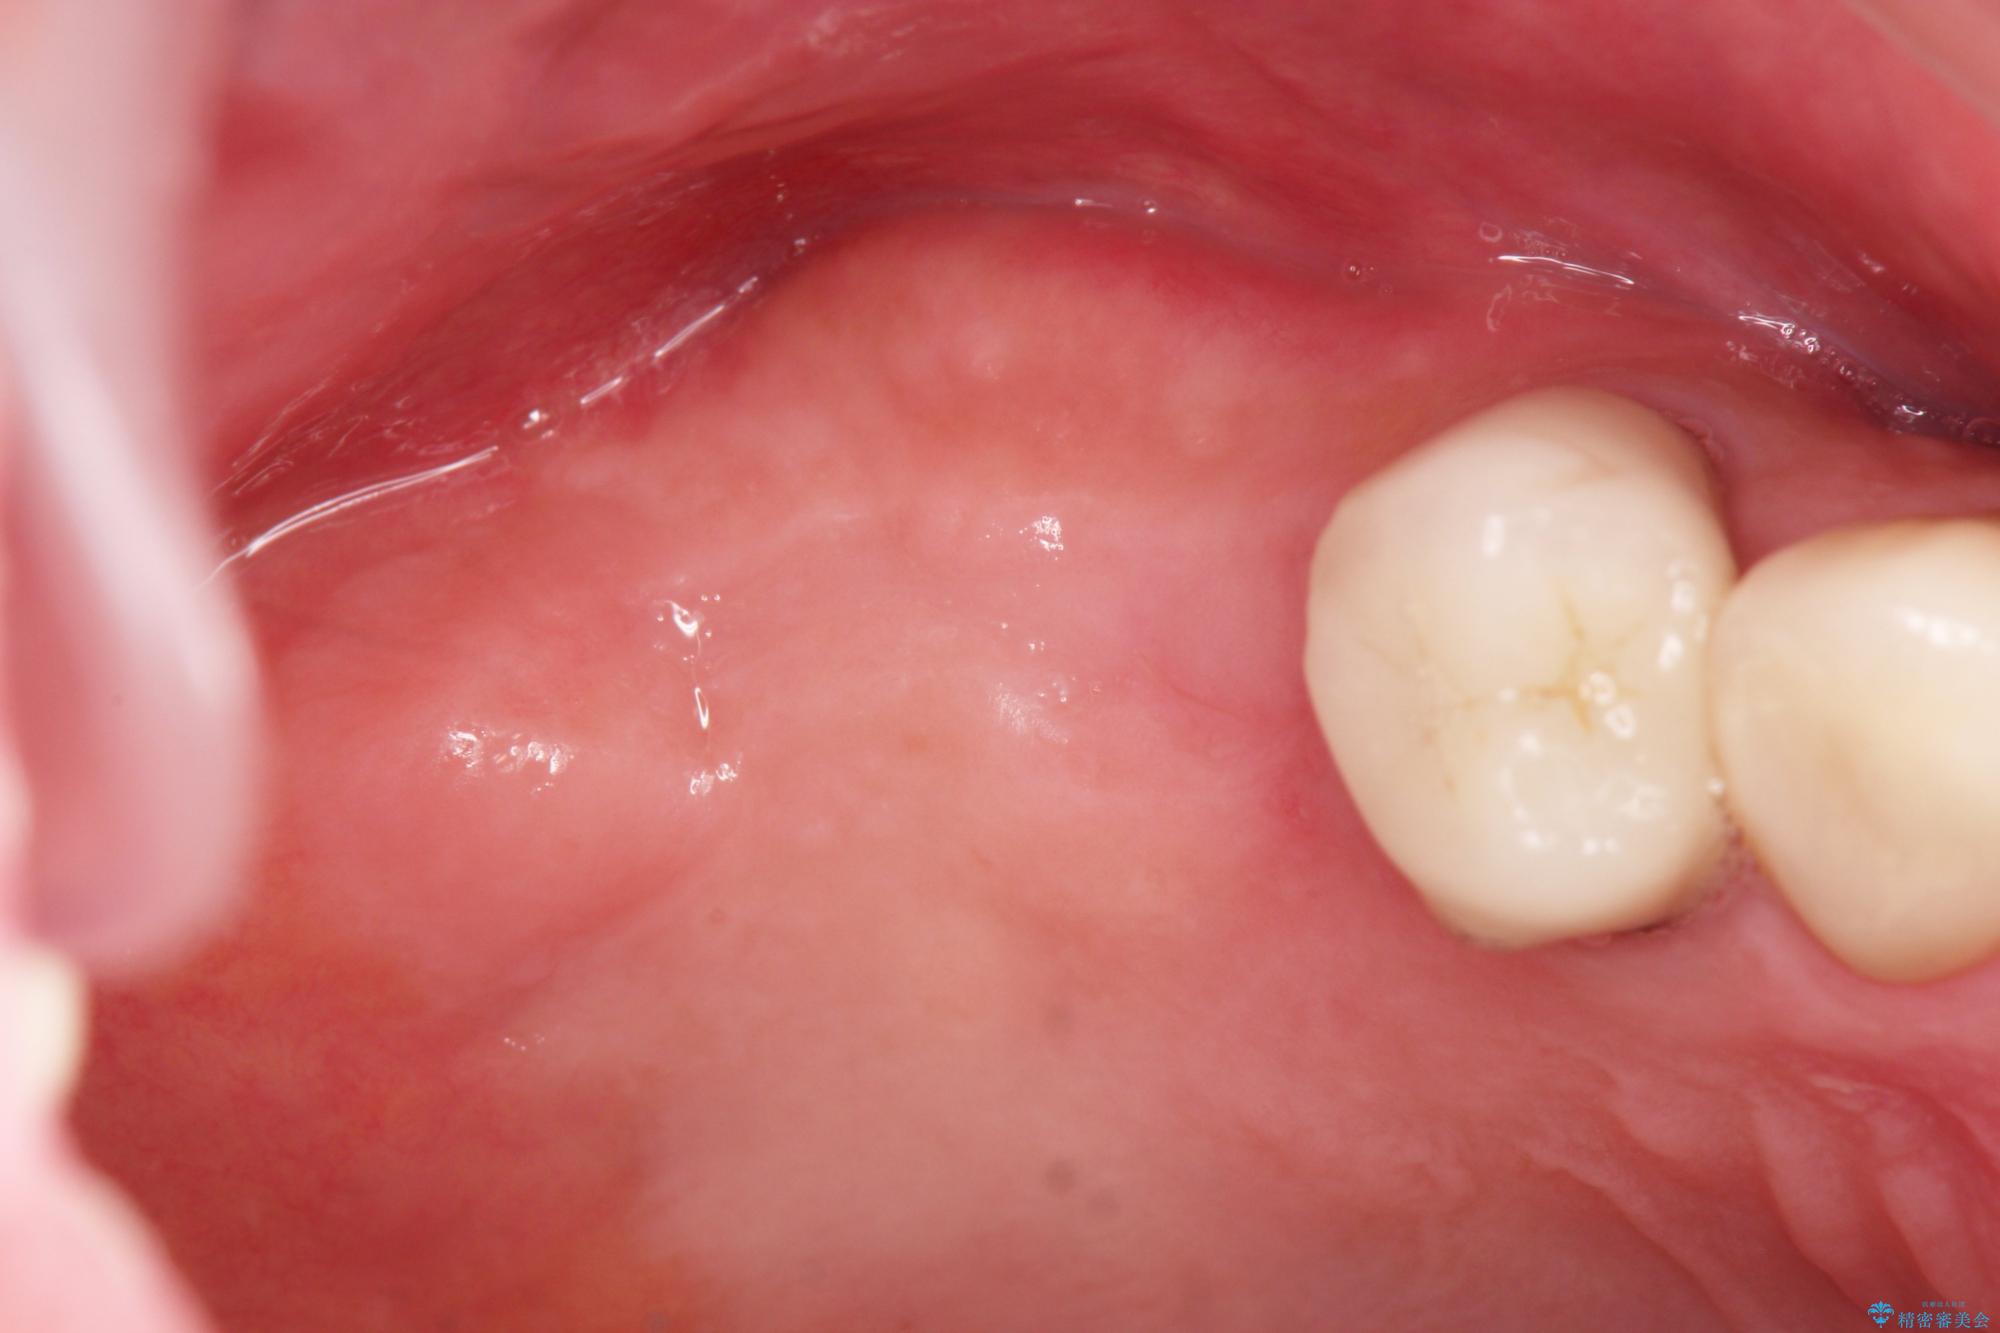

- 歯を抜いたまま放置してしまい、「やはりしっかりと噛めるような状態にしてほしい」とインプラント治療を希望され来院されました。

人工歯根であるインプラントを埋入することで奥歯でまたしっかりと噛める咬合機能を回復します。

またしっかりと噛めるようになり、食事を楽しめるようになった!と喜んでいただくことができました。